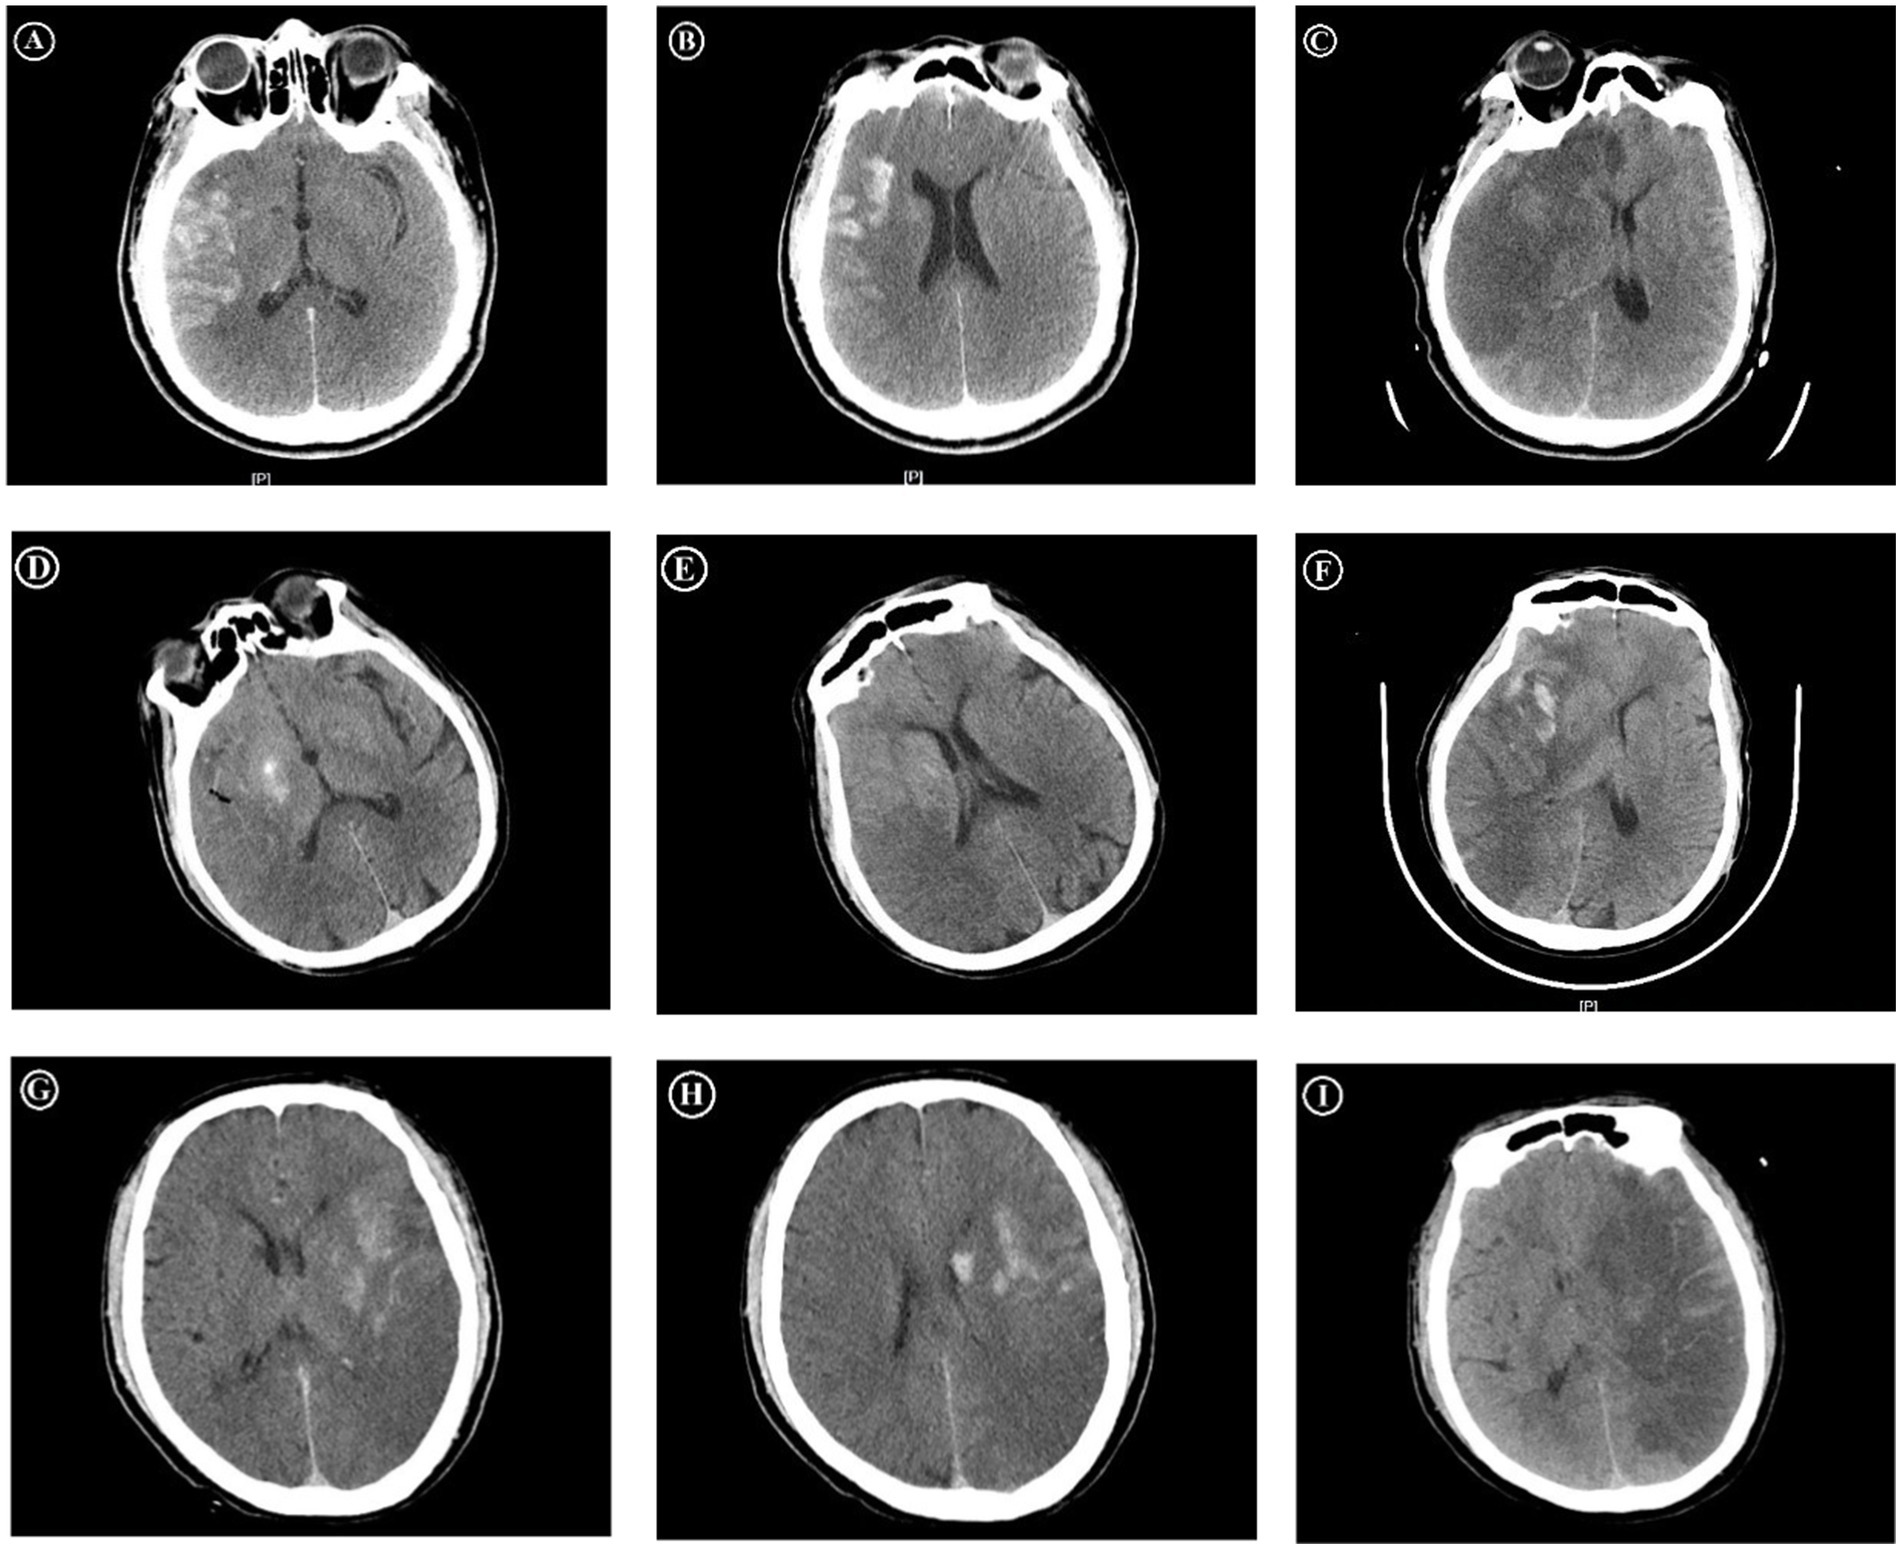

The cortex–basal ganglia subtypes of PCHDs: PCHDs were further categorized into three subtypes according to their distribution characteristics. The cortex sign was characterized by higher densities confined exclusively to the cortical regions. The basal ganglia sign was marked by higher densities restricted solely to the subcortical regions. The combined sign was defined by the presence of higher densities in both the cortical and subcortical areas (Figure 1).

Figure 1. Immediate and follow-up CT images after MT. The first patient, who presented the cortex sign with PCHDS of 7 on CT immediately after MT (A,B), developed MBE on follow-up CT (C). The second patient, who presented the basal ganglia sign with PCHDS of 9 (D,E), eventually developed MBE (F). The third patient, who presented the combined sign with PCHDS of 7 (G,H), eventually developed MBE (I). MT, mechanical thrombectomy; MBE, malignant brain edema; PCHDS, postinterventional cerebral hyperdensities score.

The scoring system of PCHDs: Postinterventional cerebral hyperdensities score (PCHDS) was used to assess the scope of PCHDs distribution. This score was based on ASPECTS, which divided the two levels of MCA territory into 10 regions. The total score was 10 points, with points deducted for each region affected by PCHDs (Figure 1).